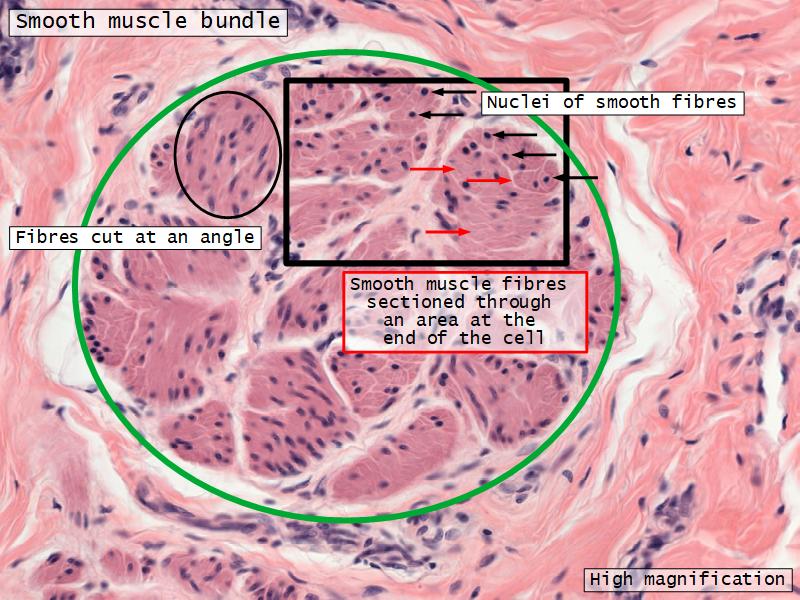

- Interlaced with smooth muscle fibres

- Smooth muscle

- Fibres and bundles